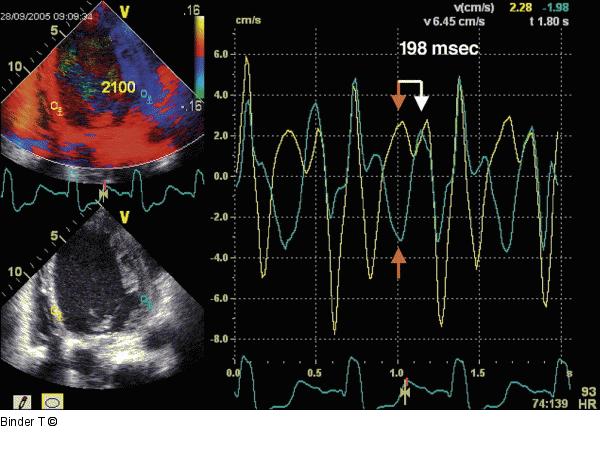

Abbildung 16: Gewebedoppler ("offline") basal laterale Wand und basales Septum Gewebedoppler (Offline-Analyse) mit dem Meßpunkt im Bereich der basalen lateralen Wand (blaue Kurve) und im basalen Septum (gelbe Kurve). Eindeutig erkennbar ist die biphasische Bewegung des Septums (oberer Pfeile) und der unterschiedliche Kontraktions- und Relaxationsablauf zwischen den beiden Wandabschnitten. |

Gewebedoppler (Offline-Analyse) mit dem Meßpunkt im Bereich der basalen lateralen Wand (blaue Kurve) und im basalen Septum (gelbe Kurve). Eindeutig erkennbar ist die biphasische Bewegung des Septums (oberer Pfeile) und der unterschiedliche Kontraktions- und Relaxationsablauf zwischen den beiden Wandabschnitten. |